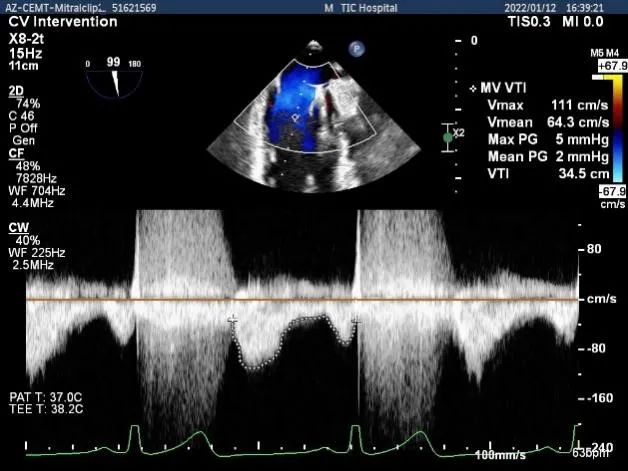

第一个夹子放置侯二尖瓣口平均跨瓣压差:2mmHg

肺静脉血流频谱逐渐恢复正向

第二个夹子放置侯二尖瓣口平均跨瓣压差:3mmHg

肺静脉血流频谱完全恢复正向